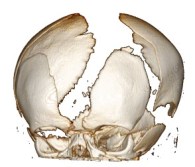

la clinique est souvent réduite à une augmentation rapide du périmètre crânien, parfois, une tuméfaction molle sous-cutanée lorsque la voûte est lysée ; au moment du diagnostic, il existe le plus souvent un tableau d’hypertension intra-crânienne souvent sévère.